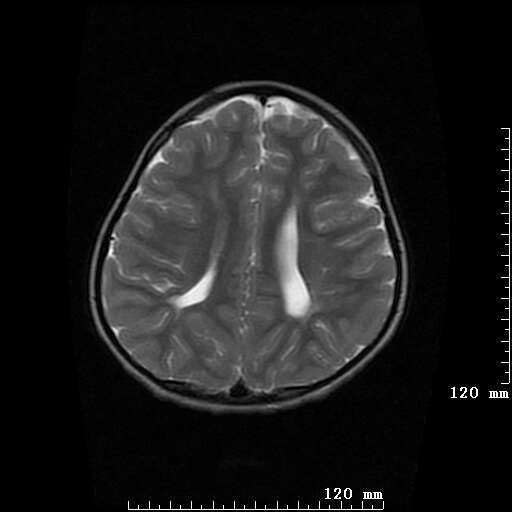

女,7岁,三岁才说话、走路。现智力尚可,走路不稳。临床怀疑大脑发育不全。

脑折质变薄,双侧侧脑室稍扩张,支持考虑脑折质发育不良

侧脑室周围白质软化症。

考虑胼胝体发育不全,髓鞘形成不良。

支持考虑胼胝体发育不全,髓鞘形成不良。

侧脑室周围白质数量减少,侧脑室不对称性扩大,左侧侧脑室后角呈方形改变,脑沟加深,结合临床考虑脑室周围白质软化症(pvl)。期待结果!

支持脑白质发育不良。